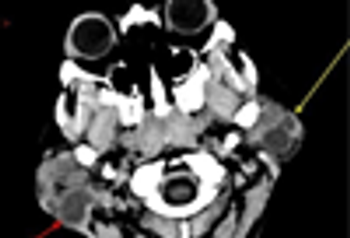

The top men's health concerns include heart disease, cancer, accidents, and chronic lower respiratory diseases. This compact slide show provides visual presentations of other clinical problems that pose a threat to men and that might be seen in primary care practice.